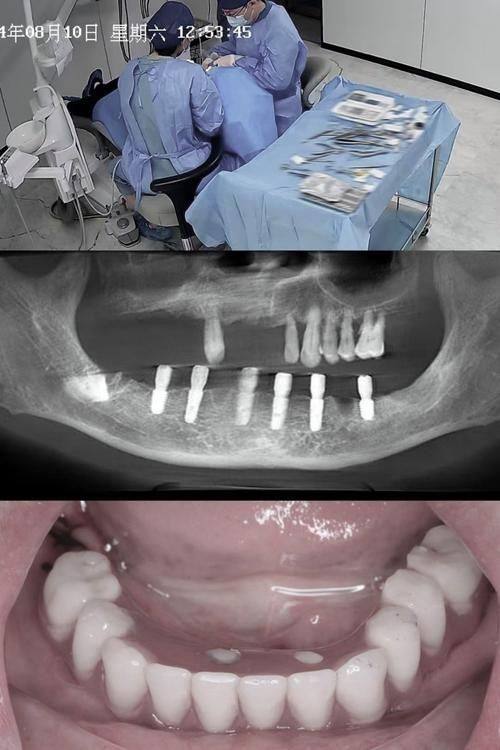

高念医生擅长的第一个项目是全口和半口种植。全口种植就是当患者全口牙齿都缺失的时候,通过种植技术为患者重新打造一口新牙。半口种植则是针对半口牙齿缺失的情况。高医生在这个项目上经验多,他会根据患者的口腔情况,选择合适的种植体,确保种植的牙齿能够稳固、美观,就像为患者量身定制了一副新牙齿一样。而且,他会在种植过程中尽量减少患者的痛苦,让患者在舒适的状态下完成治疗。

第二个擅长项目是即刻种植。即刻种植就是在拔牙后马上进行种植,这样可以节省治疗时间,减少患者的等待痛苦。高医生在即刻种植方面技术娴熟,他能够精细地把握拔牙和种植的时机,确保种植体能够顺利植入,并且与周围的组织理想融合。他就像是一位神奇的魔法师,能在短时间内为患者解决牙齿缺失的问题。

第三个擅长项目是即刻负重种植。即刻负重种植就是在种植后马上就可以承担一定的咀嚼压力,患者不用长时间等待牙齿愈合。高医生在这个项目上有自己独特的技术和方法,他会根据患者的具体情况,调整种植体的位置和角度,确保种植体能够承受住咀嚼压力,让患者能够尽快修复正常的饮食。

第三个技术优势是精细的操作。在进行种植手术等治疗时,高医生的操作非常精细。他会使用精良的设备和工具,严谨地定位种植体的位置和角度,确保种植的成效。他的精细操作就像一位非凡的狙击手,能够正确地命中目标,为患者带来更好的治疗成效。